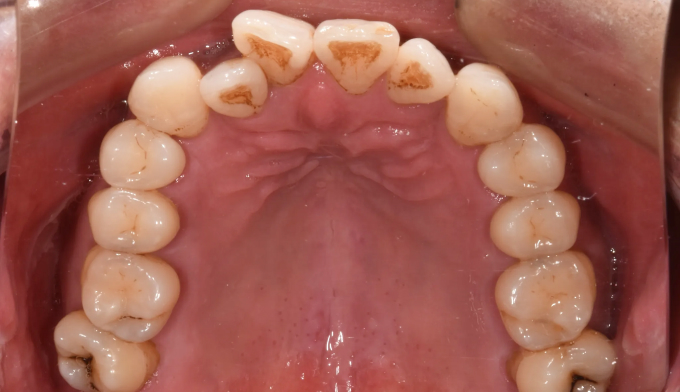

그동안 구강관리 소홀로 아래앞니 하나가 충치로 인해 소실되었으며, 동시에 골격의 주걱턱 경향으로 인해 앞니가 거꾸로 물리는 상황입니다. 아래앞니 빈공간을 임플란트나 크라운과같은 보철치료로 마무리 할 수도 있지만 교정치료를 통해 공간을 메운다면 동시에 거꾸로 물리는 앞니도 개선 가능하므로 교정치료가 보철치료보다 훨씬 효과적인 치료라고 볼 수 있습니다. 환자분의 교정치료에 대한 협조도와 이해도가 높아 비교적 이른 시간내에 교정치료가 마무리되어 매우 만족해 하셨던 케이스입니다. 총 교정기간은 14개월 소요되었습니다.